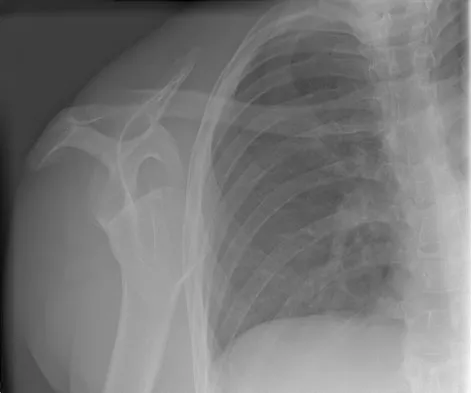

An 11-year-old boy has right shoulder pain and has been unwilling to use the arm after throwing a baseball in a Little League game 3 weeks ago. Examination reveals upper arm and shoulder tenderness with swelling. A radiograph and MRI scan are shown in Figures 27a and 27b. Management should consist of

Explanation

The radiograph is consistent with a unicameral (simple) bone cyst. The MRI scan reveals that the cyst is juxtaposed to the physis and therefore can be classified as active (latent cysts are more than 1 cm away from the physis). Active cysts are treated with aspiration and steroid injection, although repeated injections may be necessary. Curettage and bone grafting results in more reliable healing but may lead to growth arrest in active cysts. Iannotti JP, Williams GR: Disorders of the Shoulder: Diagnosis and Management, ed 1. Philadelphia, PA, Lippincott Williams & Wilkins, 1999, pp 945-946.